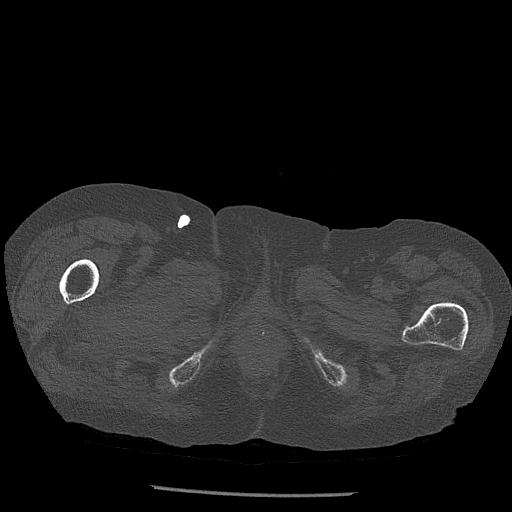

56476 8/28 4R 1/21 2R 左足関節 デジカメ写真 72歳女性 右足関節AS